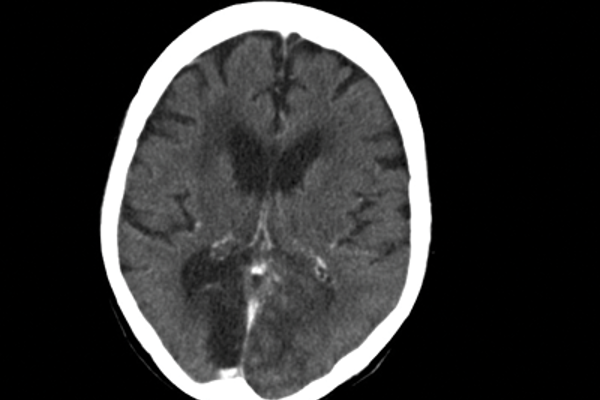

Cortical blindness